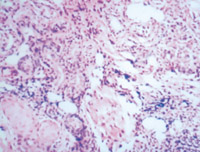

5-2-3 傷后第3天,表皮細(xì)胞空泡化,真皮淺層膠原纖維玻璃樣變,真皮內(nèi)散在炎細(xì)胞浸潤  HE×100